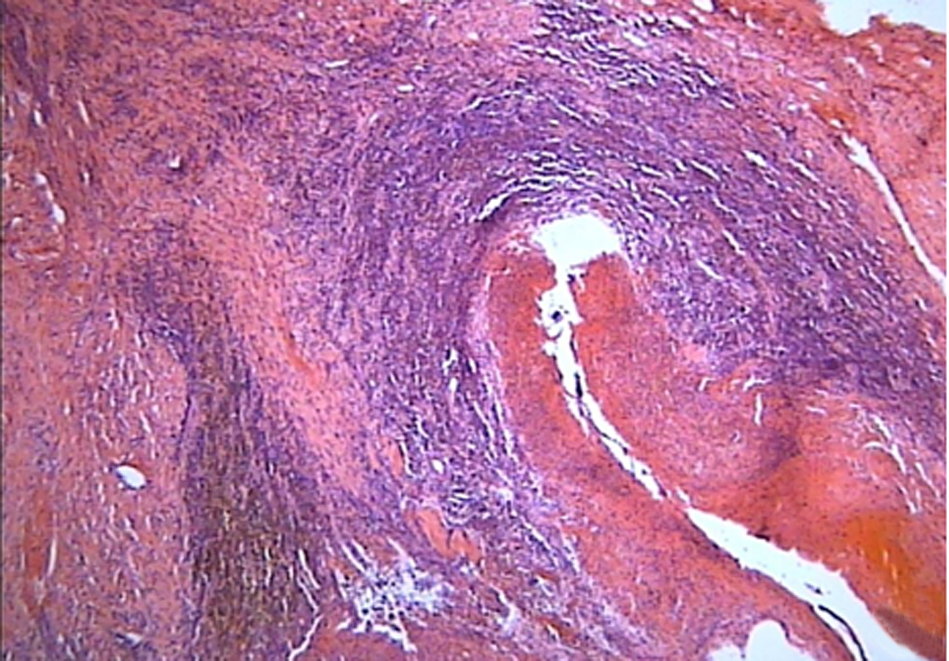

74例特发性非硬化性门静脉高压症患者的临床特征分析

韦新焕, 张晶, 张志丽, 刘焱, 范丽娟, 宋健, 张月宁

2023, 39(7): 1570-1577. DOI: 10.3969/j.issn.1001-5256.2023.07.010

摘要(918) HTML (247) PDF (2041KB)(108)

摘要:

目的  特发性非硬化性门静脉高压(INCPH)是一种少见的引起门静脉高压的病因,对INCPH患者的临床特点进行分析以辅助诊断及鉴别诊断。  方法  选取北京佑安医院2019年1月—2022年7月经肝穿刺病理明确诊断为INCPH的住院患者74例,并以同期住院的332例肝硬化患者作为对照组,记录其人口学指标、实验室指标、胃镜、肝弹性检查、病理检查及并发症等资料,进行组间差异比较,并根据受试者工作特征曲线(ROC曲线)评价LSM、APRI、FIB-4对INCPH的鉴别诊断能力,采用DeLong检验方法进行ROC曲线下面积(AUC)比较。符合正态分布的计量资料两组间比较采用成组t检验,非正态分布的计量资料两组间比较采用Mann-Whitney U检验。计数资料两组间比较采用χ2检验。  结果  INCPH患者中46.55%的患者起病时无明显症状,43.24%患者曾被误诊为肝硬化。INCPH患者合并消化道出血比例明显多于肝硬化患者(62.16% vs 41.27%,χ2 =10.67,P<0.01),但合并中-重度腹水患者比例明显少于肝硬化患者(16.21% vs 29.82%,χ2=34.98,P<0.01),无肝性脑病发生。病理方面,89.19%(66/74)患者病理表现为典型的闭塞性门静脉病。INCPH患者肝功能指标、MELD评分、Child-Pugh评分等指标明显优于肝硬化患者,肝硬度值[9.05(7.18~12.33) vs 25.32(16.21~47.23),Z=-8.41,P<0.01]、APRI评分[0.70(0.41~1.28) vs 1.35 (0.80~2.39),Z=-6.21,P<0.01]、FIB-4指数[2.99(1.62~4.81) vs 6.68(4.06~10.42),Z=-8.39,P<0.01] 均较肝硬化低。LSM、FIB-4、APRI对INCPH与肝硬化患者具有很好的鉴别诊断能力,尤其是LSM的AUC达到0.92(0.87~0.96),敏感度和特异度分别为92.68%和81.60%。  结论  INCPH患者起病较隐匿,门静脉高压相关并发症发生率较高,而肝功能相对较好,尤其是LSM<14.5 kPa的患者,临床遇到此类患者需警惕INCPH可能。